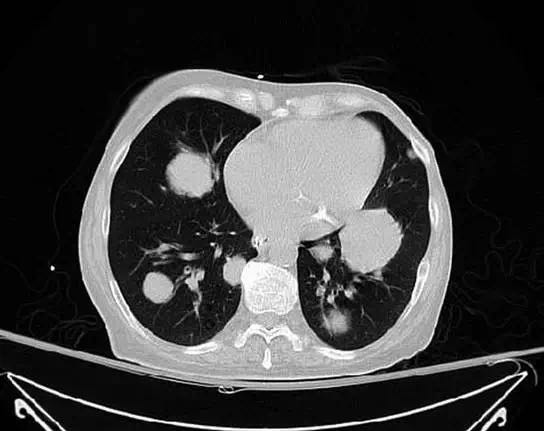

女,62岁,无显著既往史,在家中发现无意识而送医。患者进行紧急插管并就诊于急诊。检查发现患者有肾功能衰竭合并高血钾。胸部X线(图1)显示多发大的结节,高度提示肺转移。胸部(图2)、腹部和骨盆(图3)CT扫描显示毗邻膀胱的盆腔有大肿块,伴双侧肾积水,并有多发较大的空洞肺结节。盆腔肿块活检确诊为高度病变的膀胱移性细胞癌。遗憾的是,病人不接受包括化疗在内的任何侵袭性干预措施,并选择了临终关怀和姑息治疗。 诊断后1个月,患者去世。

肺部转移结节多呈大小不一、边界清楚的圆形结节,大小不同是由于瘤细胞转移到肺部的时间不同所致,边界清楚是由于充实性生长的癌结节与周围含气正常肺组织之间有良好的自然对比所致。